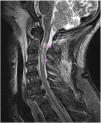

Sixty-seven-year old male without known past medical history. He suffered from syncope and cardiorespiratory arrest (CRA) while riding his bicycle and was thrown off the road. He recovered his pulse after 34min after performing basic and advanced cardiopulmonary resuscitation maneuvers. The presence of ischemic heart disease, pulmonary thromboembolism, brain hemorrhage, and ischemic disease are discarded as causes for the CRA. The cerebral magnetic resonance imaging performed showed a fracture at the base of the odontoid process (green arrow) without displacement and small anterior epidural hematoma (indicated by discontinuous white arrows) without significant mass effect (Fig. 1). All of it accompanied by a spinal cord hemorrhagic contusion (pink arrows) from the C2 up to the C3 (Fig. 2). The patient progression was poor, and he died six days after admission at the intensive care unit.